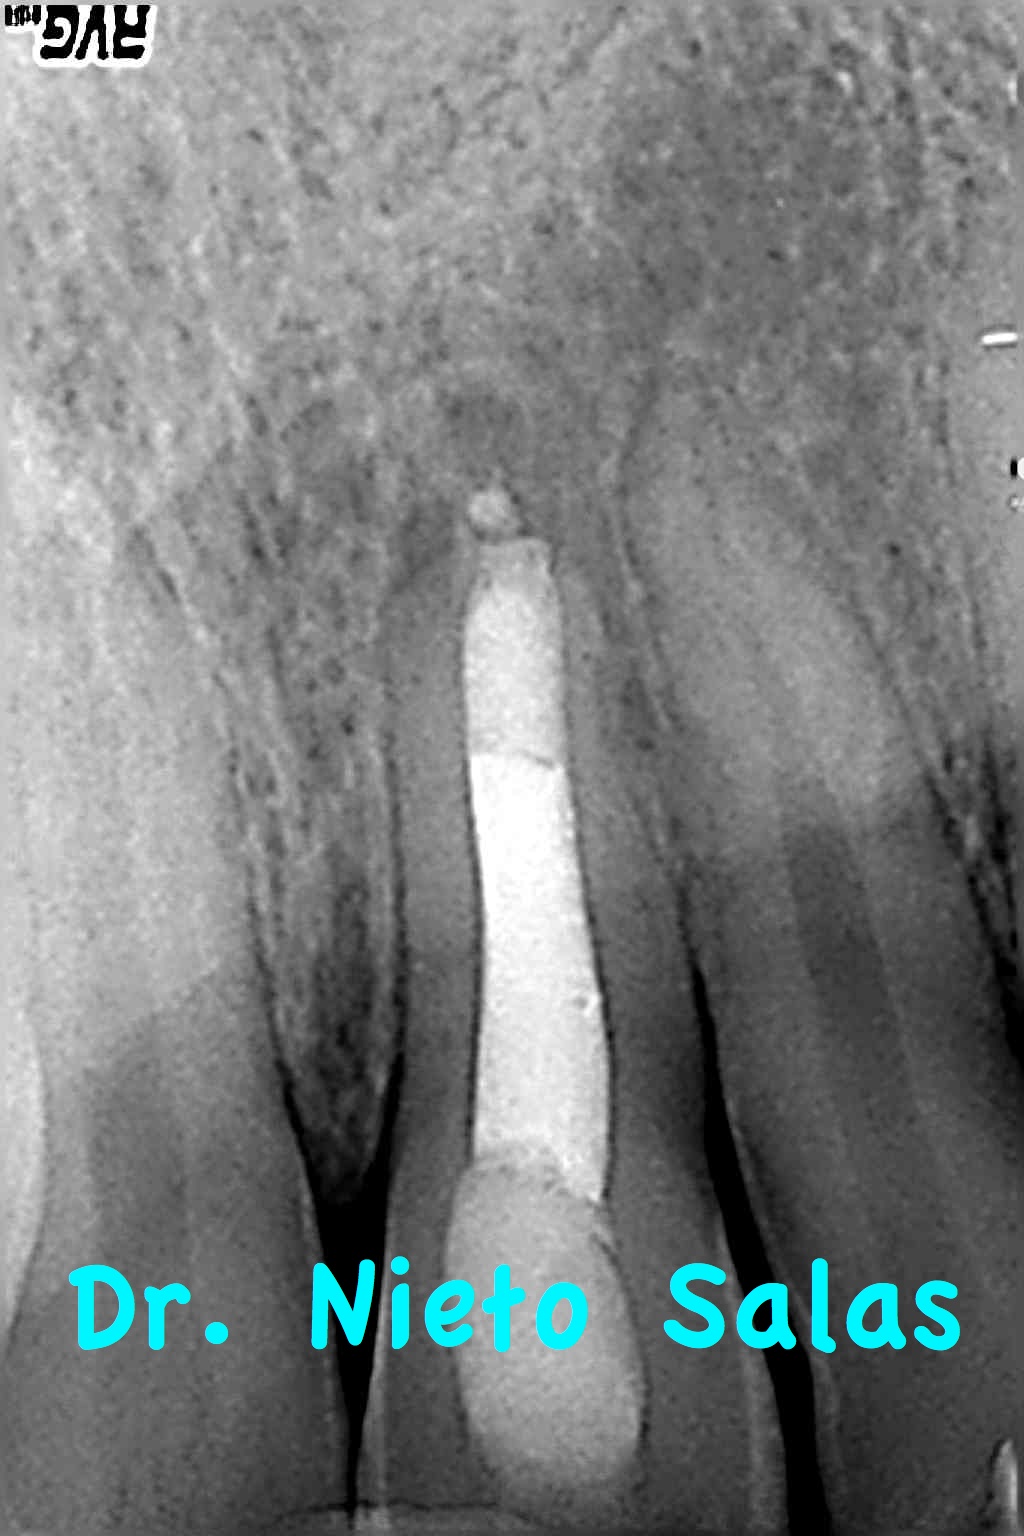

Es un tratamiento que hicimos colocando una barrera apical con M.T.A., consiguiendo un sellado apical posteriormente rellenamos el tercio medio coronal (backfilling) con gutapercha inyectada.

Se le citó a revisión a los 9 meses y vimos que el paciente no refería sintomatología y que la lesión presentaba una evolución positiva.